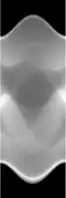

| Fantasma de Shepp-Logan; Transformada de Radon; y Transformada de Radon inversa | ||

Existe un algoritmo inverso de la transformada de Radon computacionalmente eficiente para el caso bidimensional llamado retroproyección filtrada. Primeramente consideremos el operador adjunto de :

Este operador recibe el nombre de 'retroproyector' puesto que coge las proyecciones sobre las rectas y las 'esparce' o retroproyecta para producir una imagen. Se puede observar como este operador no es la transformada inversa de Radon.

lo que significa que la imagen original puede ser recuperada del 'sinograma' aplicando un filtro rampa (sobre la variable ) y entonces retroproyectando. Como que el paso de filtrado puede ser implementado de forma eficiente (mediante técnicas de procesamiento digital de señales) y la retroproyección no es más que una acumulación de valores en los píxeles de la imagen, resulta un algoritmo altamente eficiente, por lo que se trata de un algoritmo ampliamente usado.